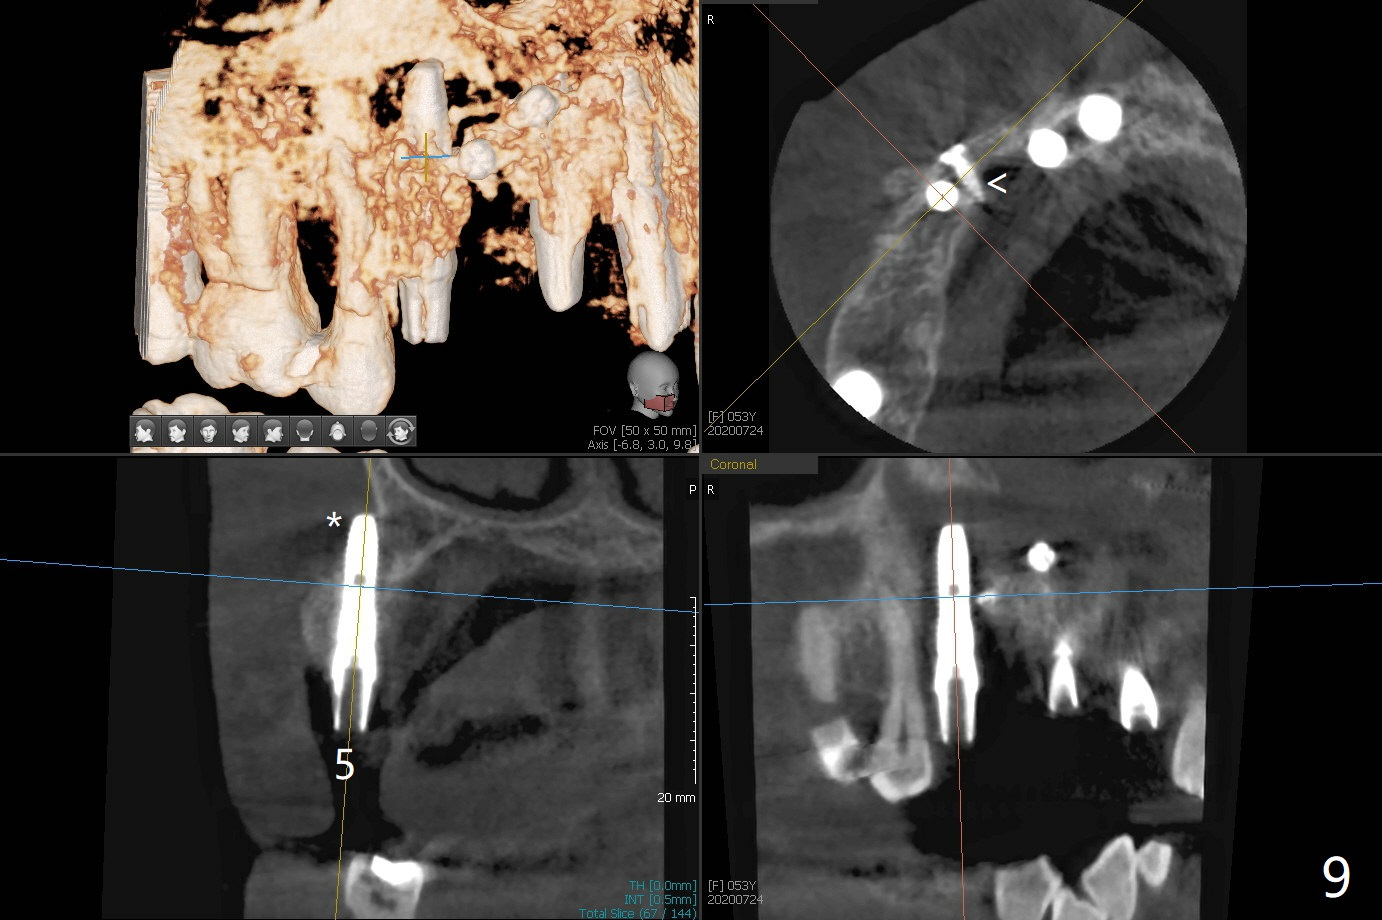

这个病例材料送到实验室作导板,实验员实在为难,只好徒手做。五号牙拔除证实颊侧骨板完全丧失,应该做位点保留(图一),但是病人非常恐惧,颊舌侧向牙槽窝好像很宽,开始尽量在舌侧建立钻洞,好像舌侧骨板太薄,又在稍微颊侧钻洞(图二),使用简易suction down stent控制钻洞方位。钻头大时,颊侧根尖有震动感觉,当时不明白为什么,稀里糊涂的植入3.8乘13毫米植体,扭力低,唯一欣慰的是颊侧放置PRF膜和粘性骨似乎到位(到根尖;图三:S),放置基台时,下面植体一起旋转,木已成舟,再次在基台周围放置骨粉。

在6,7号牙位牙槽嵴切口,翻瓣,找不到上次放置的tenting screw,不过7号牙位骨质虽然低,够宽的,开始钻洞(图四),植入3.8乘8.5毫米植体,扭力足够(图五),近中舌侧暴露螺纹堆加骨粉(图五*),然后放置基台,再次在后者周围放置骨粉(图五至七),覆盖两张PRF膜后缝合(图八),最后在三个箭头周围放置牙周敷料。术后CT显示植体与tenting screws(图九,十箭头)有一定距离,但是5号牙植体颊侧根尖穿孔(图九 *)。如果植体不脱落,需做侧方切口植骨。术后七天7号植体腭侧肿胀(图十一 *),切开没有脓水,插入牙胶尖,它末端指向7号植体周围tenting screw。后者可能需要拔除,同时5号牙颊侧根尖植骨,但是为时太早,可能打搅骨粉生长。术后两周腭侧肿胀没有消失,但是不痛,继续观察。术后接近6个月,软组织正常(图十三),但是5,7植体周围没有骨质(图十四,五)。由于近中tenting screws周围软组织触痛(局麻不全情况下),螺钉取出(图十六,七(*)),而远中螺钉好像有帮助5植体螺纹骨粉撑起,所以留下(腭侧穿孔部分去除),最后放置粘性骨粉(图十八:*)和PRF膜(两张由7基台打孔固定)。